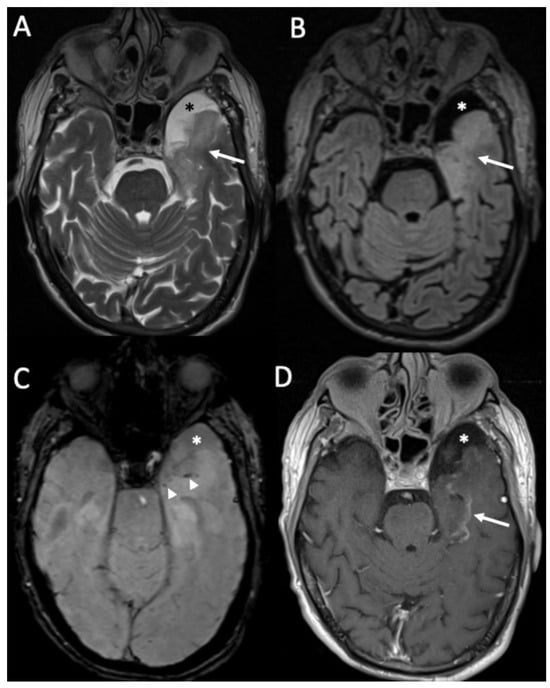

| Tuberculosis | • Leptomeningeal enhancement in the basal cisterns • Hydrocephalus very common • Infarcts in the basal ganglia due to vasculitis • Possible concomitant tuberculomas or miliary tuberculosis |

| Cryptococcus Neoformans | • Leptomeningeal enhancement • Cryptococcoma • Gelatinous pseudocysts |

| Candida albicans | • Microabscesses • Vascular lesions |

| Aspergillus fumigatus | • Abscesses • Vascular lesions |

3. Tuberculous Meningitis/Meningoencephalitis

4. Fungal Meningitis